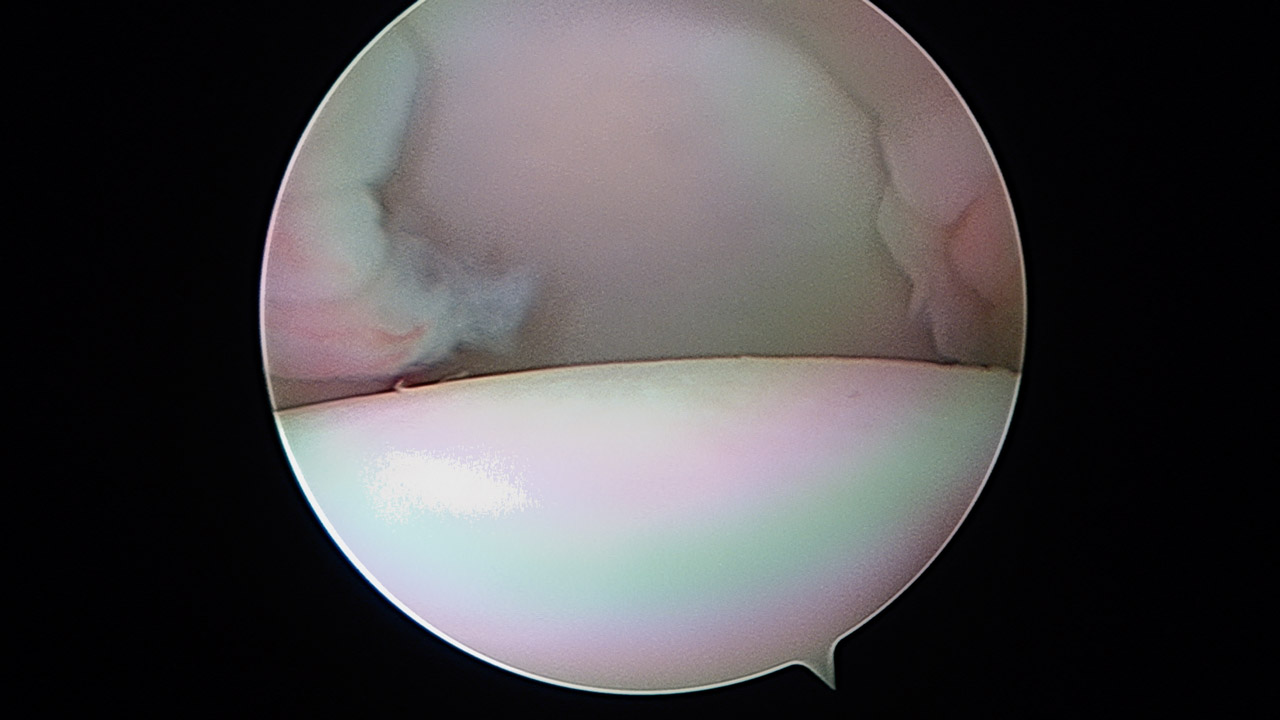

Ligamentoplastia anterior de hombro. Técnica quirúrgica

Anterior shoulder ligamentoplasty. Surgical technique